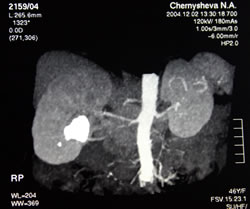

КОМПЬЮТЕРНАЯ

ТОМОГРАФИЯ С БОЛЮСНЫМ КОНТРАСТИРОВАНИЕМ: |

|